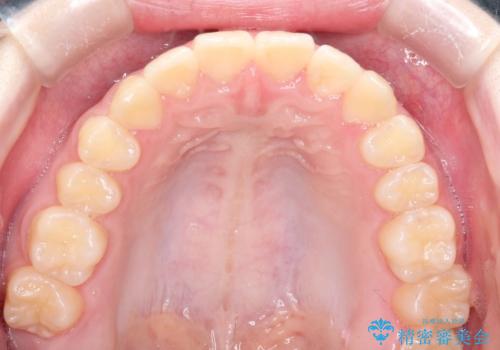

上下の前歯のガタガタを目立たず治したい インビザラインによる見えない矯正

受験生ということもあり、来院頻度が少ないマウスピース矯正で治療が終了できたことに満足いただけました。

上下の正中が一致していませんが、受験を控えているためご本人の希望もあり、いったん終了とさせていただきました。